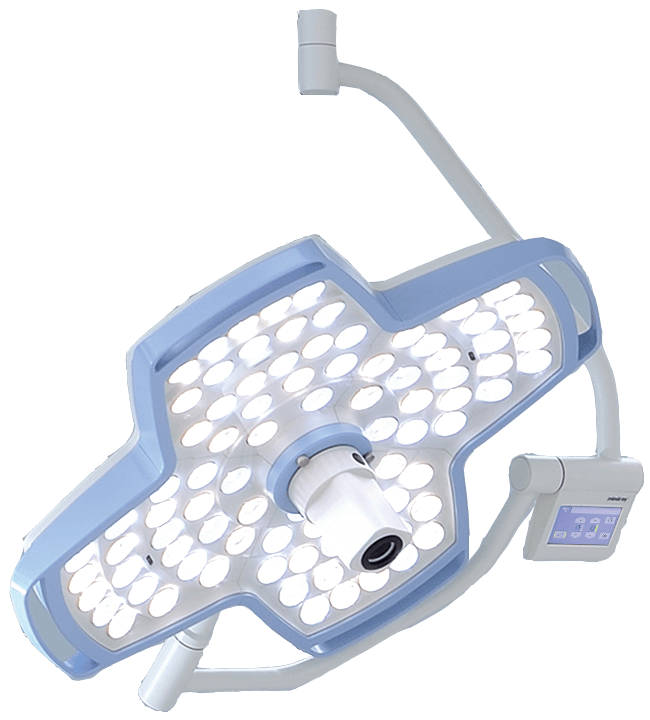

- ¬ЈLights